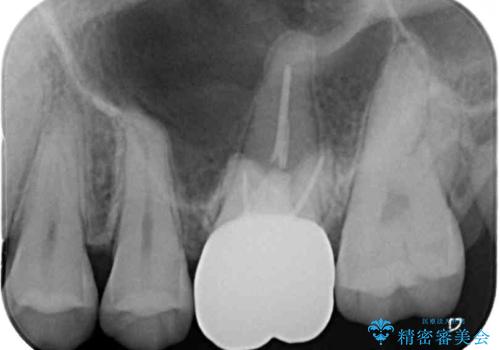

左上の銀歯は、銀歯の下に金属の土台が入っているため、その土台を除去し、ファイバーコアにやり替えて、オールセラミッククラウンにて補綴することとしました。

適合の良いセラミック治療は、むし歯再発のリスクが低いです。

目立つ銀歯がなくなり、患者様は大変満足されました。